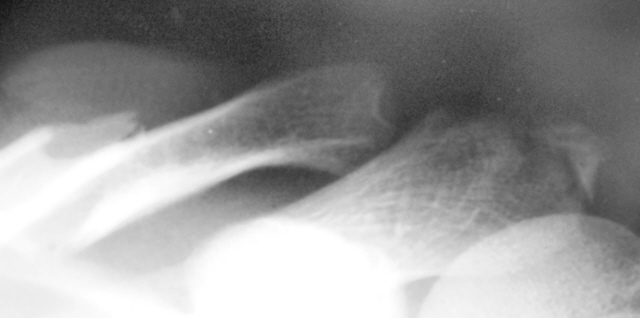

Это не отломок акромиона, а его апофиз.

Вот тоже апофиз, чуть побольше только.

Изображение